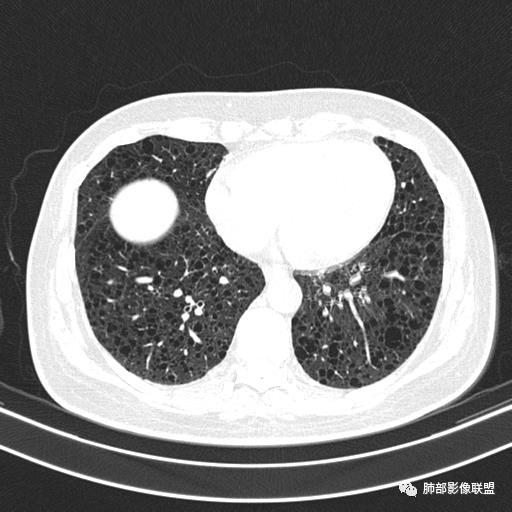

CT平扫示双肺弥漫分布大小不等囊状薄壁透光区,无内、中、外带分布差异,间质稍示增厚。拟LAM

中年女性,双肺弥漫性磨玻璃密度影,并见弥漫性分布大小不一囊腔,壁薄,形态规则,考虑lam,鉴别苯中毒肺损伤致间质改变

中年女性育龄期妇女,咳嗽气喘,无吸烟史,有苯吸入史。影像:双肺弥漫均匀小囊腔,无明显分布优势,囊腔形态欠规则,壁薄,部分囊腔边缘血管征,伴双肺弥漫磨玻璃影,无结节,考虑lam,鉴别苯中毒肺损伤,囊腔多有分布优势,小叶中心分布为主,形态规整等

女,46,活动性气喘1年。苯吸入史半年。胸部CT:两肺弥漫囊腔,上至肺尖,下至肋膈角,形态类似小囊腔。考虑:LAM,鉴别LIP,BHD,PLCH等。

双肺多发大小相近的囊状影,分布趋势趋于一致,中年女性,考虑LAM。部分囊内见血管及分隔影,小叶中心性肺气肿代排

CT表现:双肺弥漫大小不等的薄壁囊腔,囊壁<2mm,外形规则,血管影多位于囊腔周围,囊腔之间肺组织正常,随着疾病进展到晚期,囊腔变大、增多,不可胜数,囊腔可融合成较大的囊,与肺气肿相似,形成间质性肺纤维化。部分病例可出现结节影。